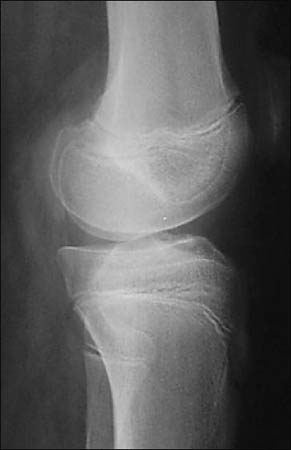

Figura 6: Rx Frente Postoperatorio, correcta posición de anclajes óseos.

Figura 7: Rx perfil Postoperatorio, correcta posición de anclajes óseos, correcta altura patelar.

Se realizaron radiografías de control en el postoperatorio inmediato. (Figs. 6, 7)

Se realizó el diagnóstico clínico de la lesión (impotencia funcional, dolor y brecha infrapatelar) y luego los métodos de imágenes complementarios confirmaron las lesiones. Mediante RNM se pudo esta- blecer el nivel de la lesión, con 9 desinserciones a nivel del polo distal de la rótula y 1 rotura mediotendinosa en el tendón patelar.